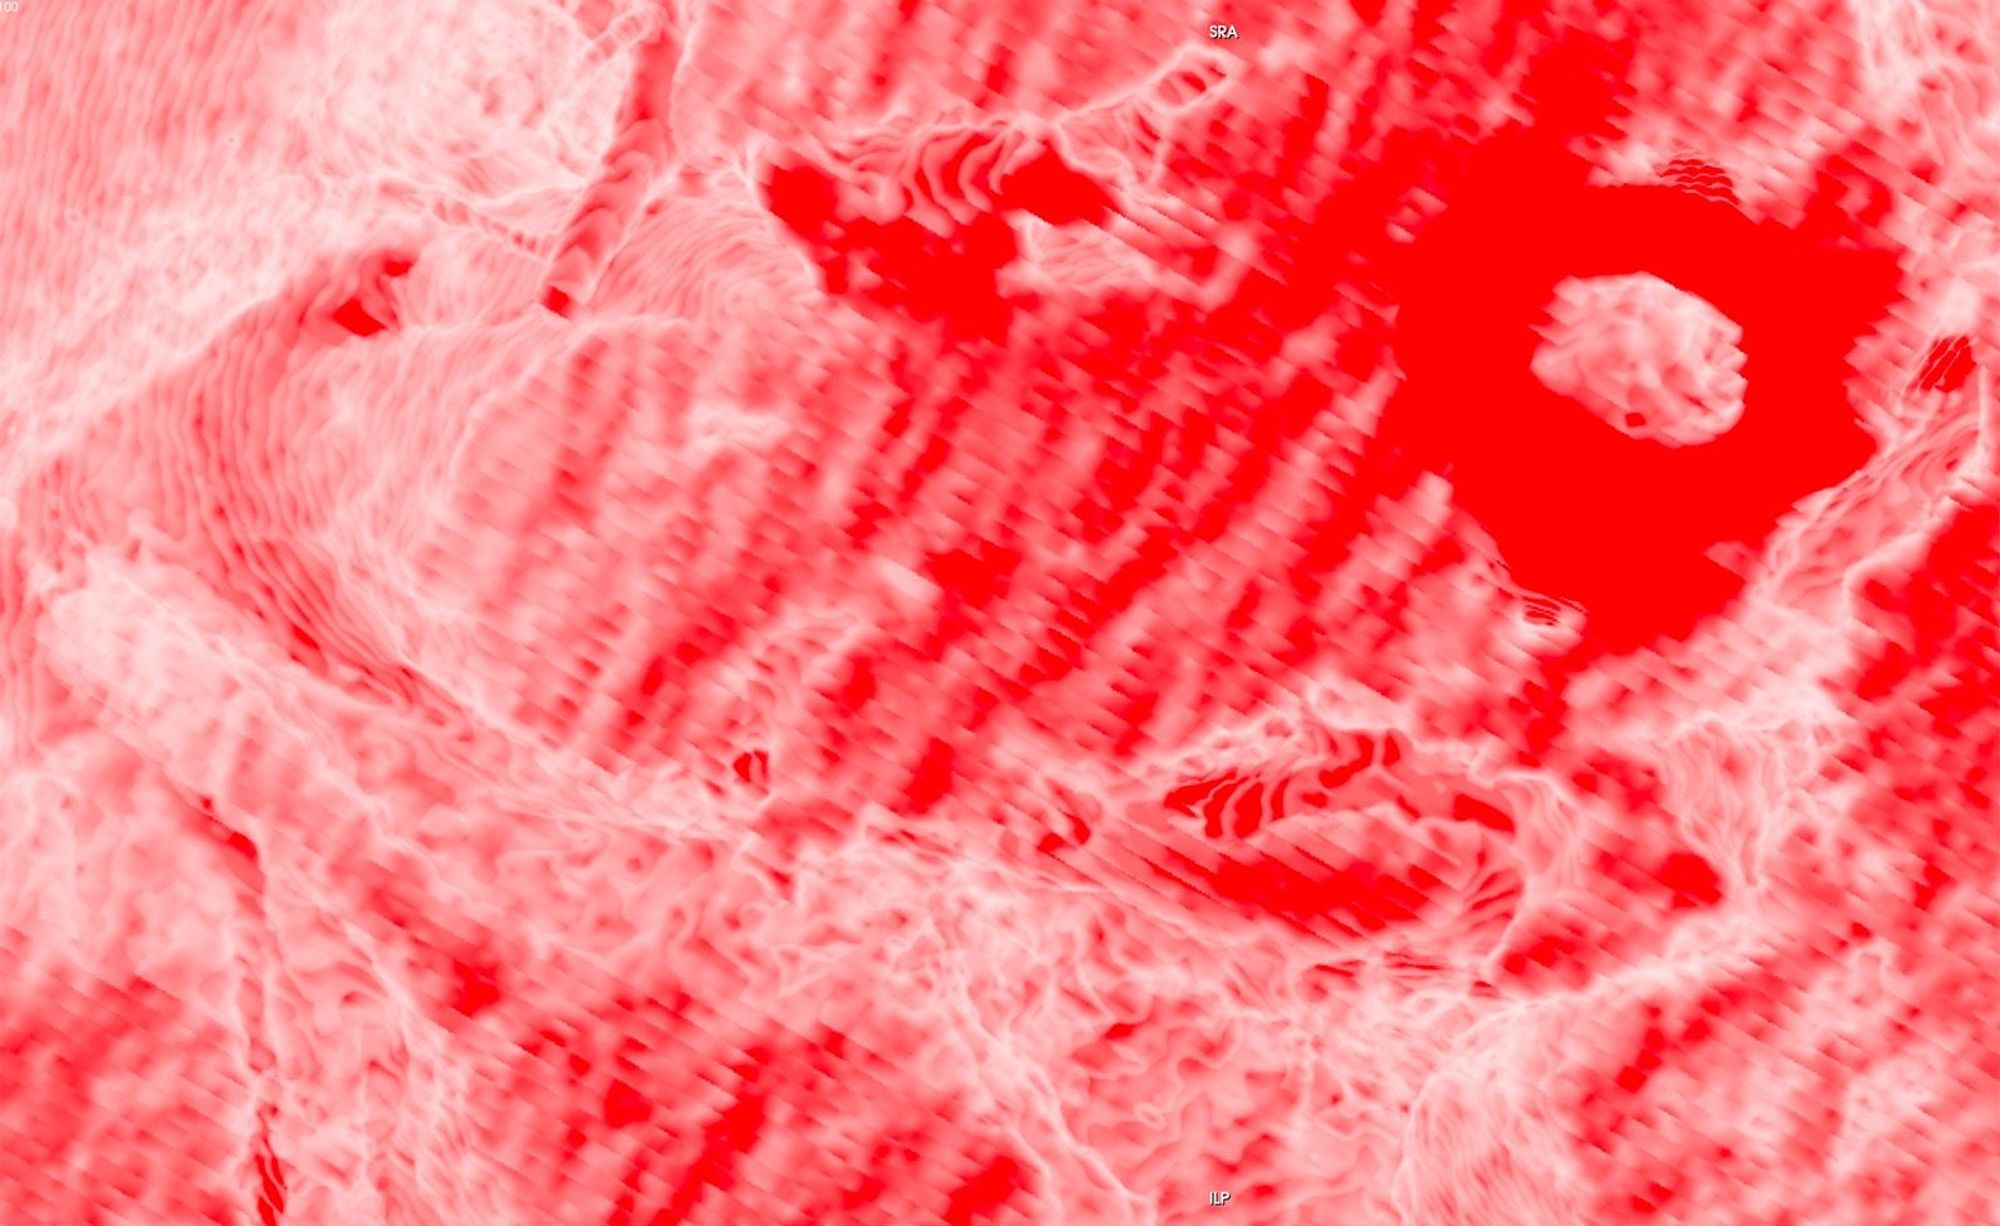

Chasing Intensities considers the body through its relationship to contemporary medical imaging technologies.

In this project, I look at the visual limit between the inside and the outside, the inner and the outer. I combine different visual approaches to materialise the body, using medical imagery, photography from manuals and radiology software. Decontextualised from their origin, these images speak of medicine’s relationship to both sex and violence, and remind us that, in medicine, to go into the body is always to go into the image first.